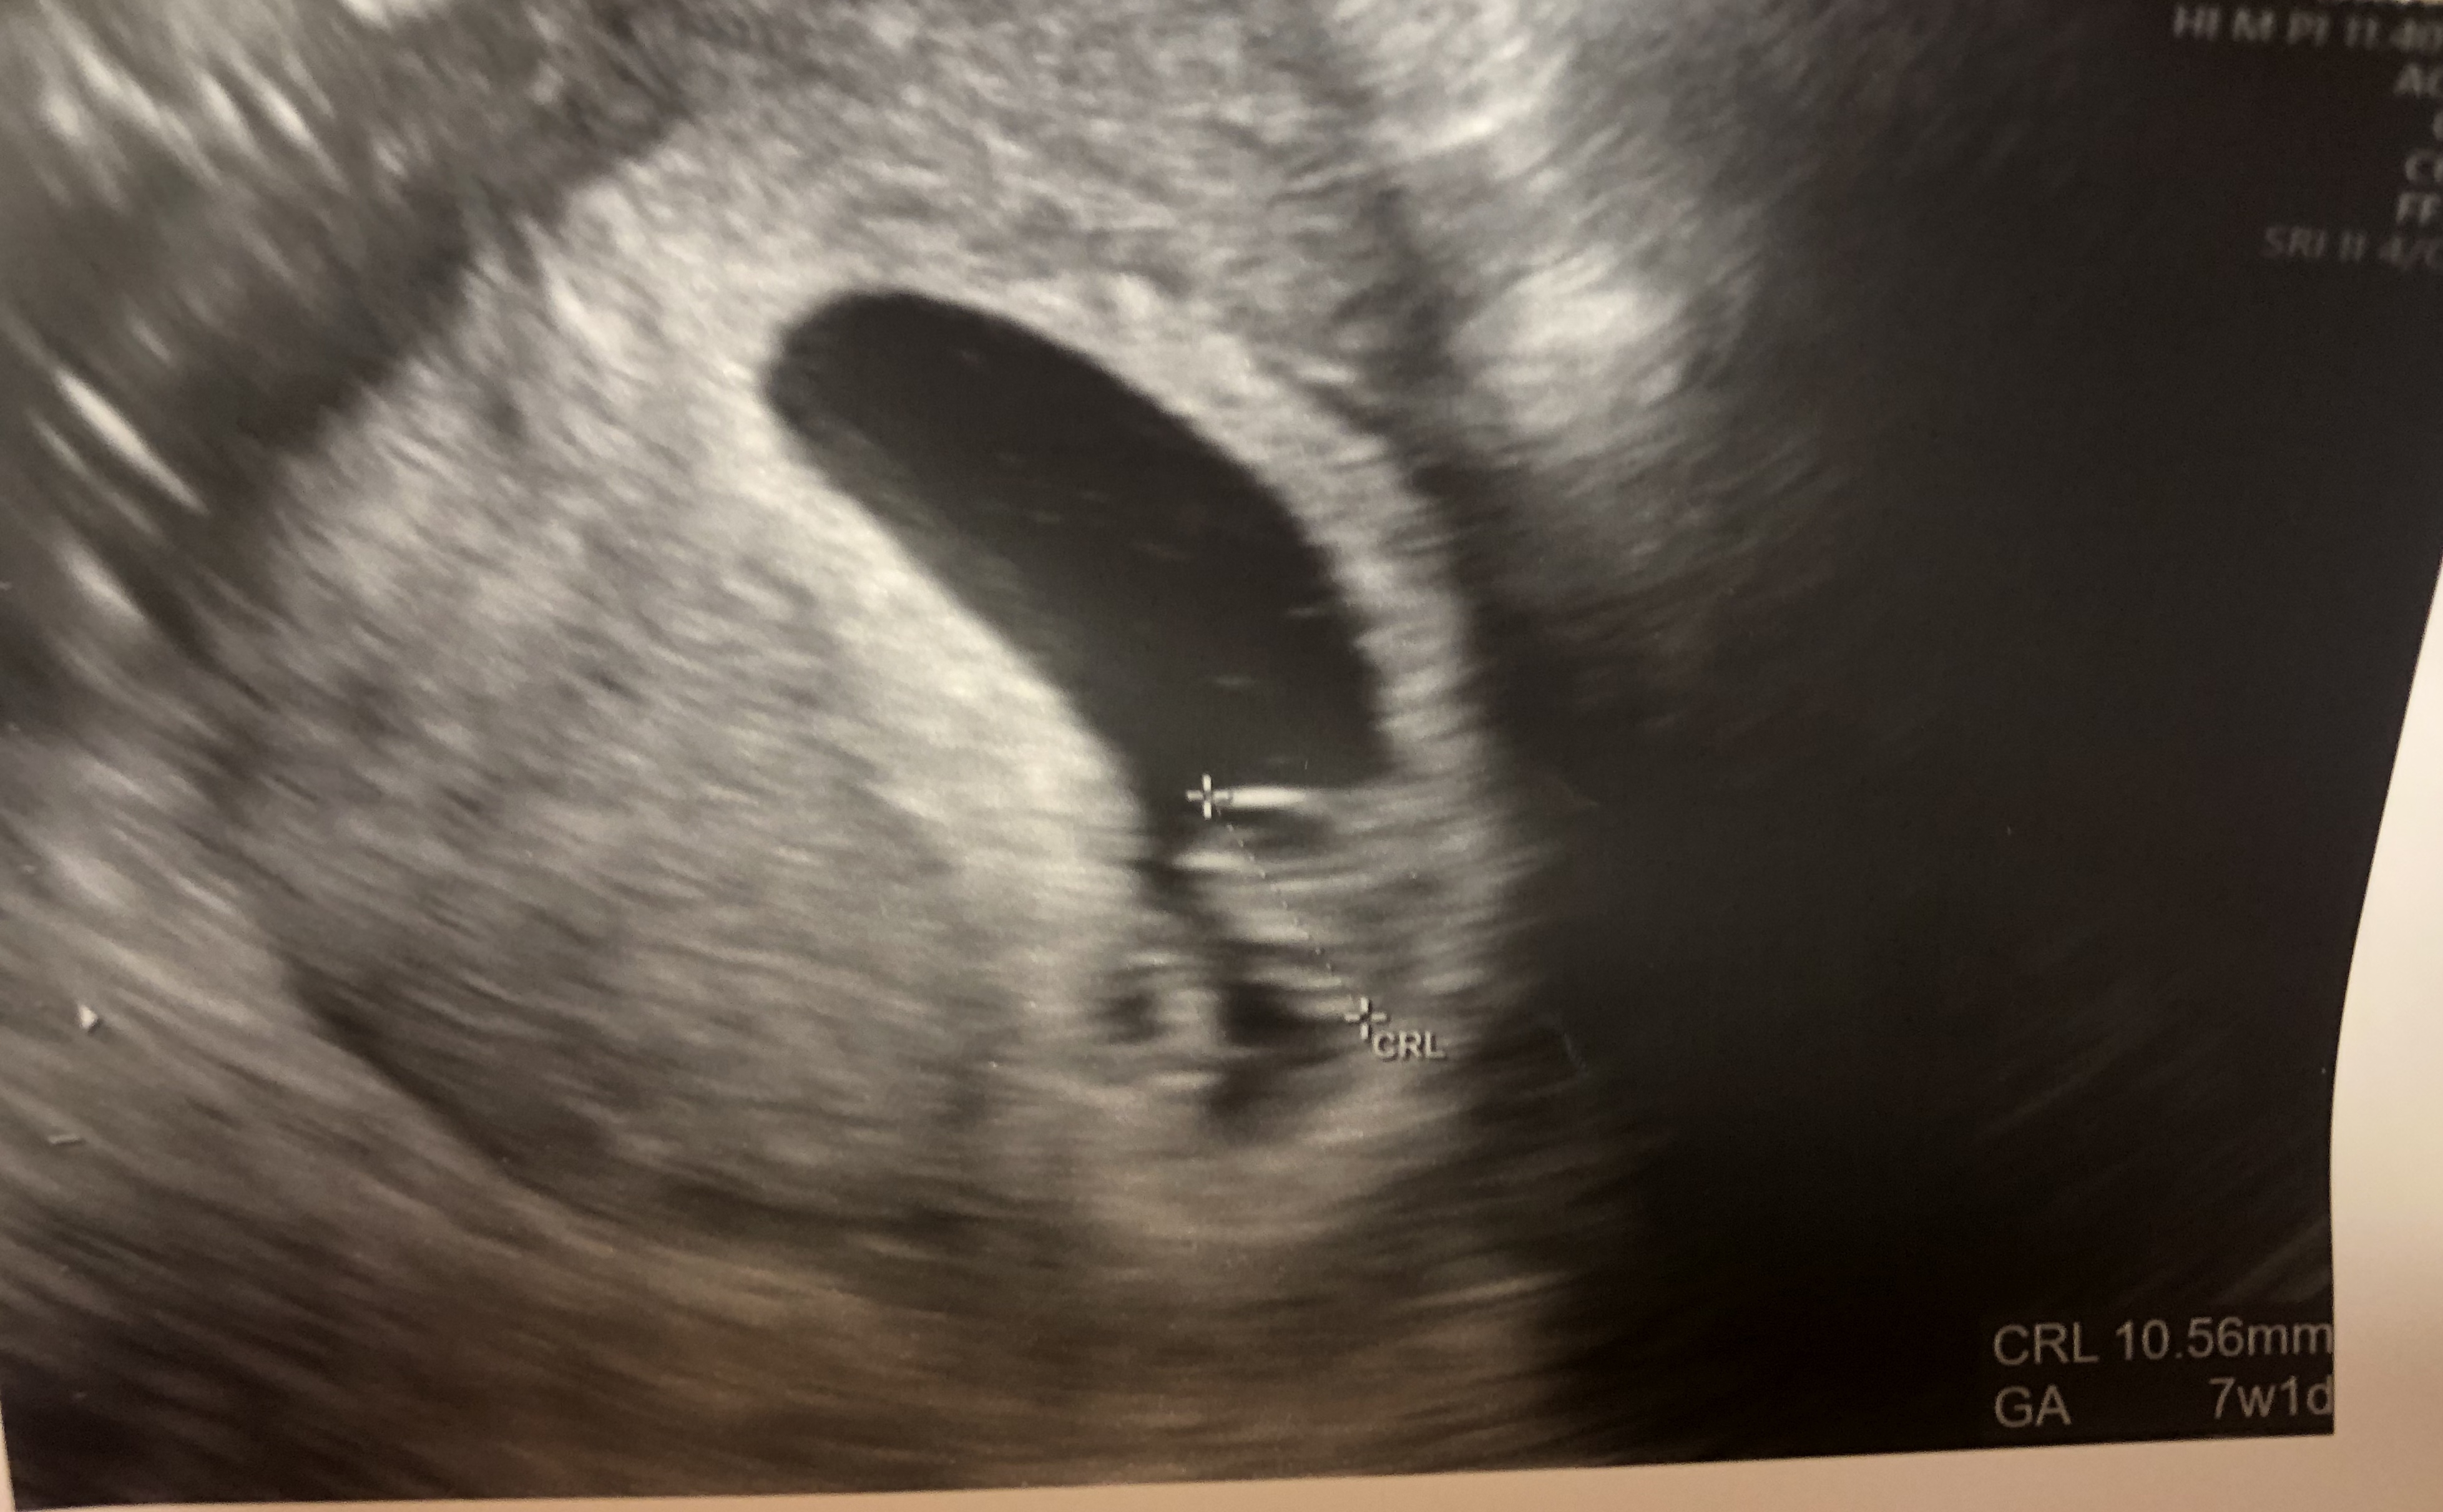

Baby looked perfect this morning and is measuring 10w3d exactly which is what I am today! Heart rate of 170. We are over the moon, it was so exciting to see him again and he was so wiggly!!!